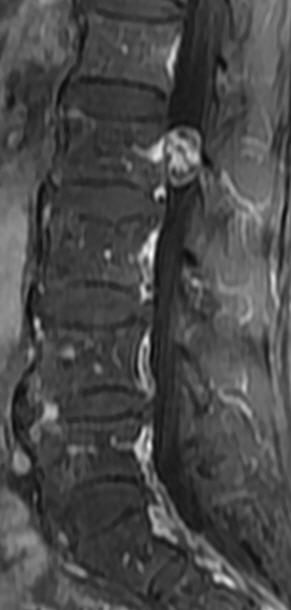

MRI

可提供腰椎管的矢状面、冠状面和轴位横断面上的影像。椎管狭窄以T2加权像显示较好,脑脊液为高信号,产生所谓“脊髓造影”的效果,而骨质增生,骨赘、间盘均为低信号,能清晰地显示椎管狭窄,以及对脊髓的压迫情况。但对肥大的黄韧带、骨质增生等的判断则不如较高清晰度CT扫描。

腰椎正常MRI解剖。

腰椎管狭窄MRI表现。